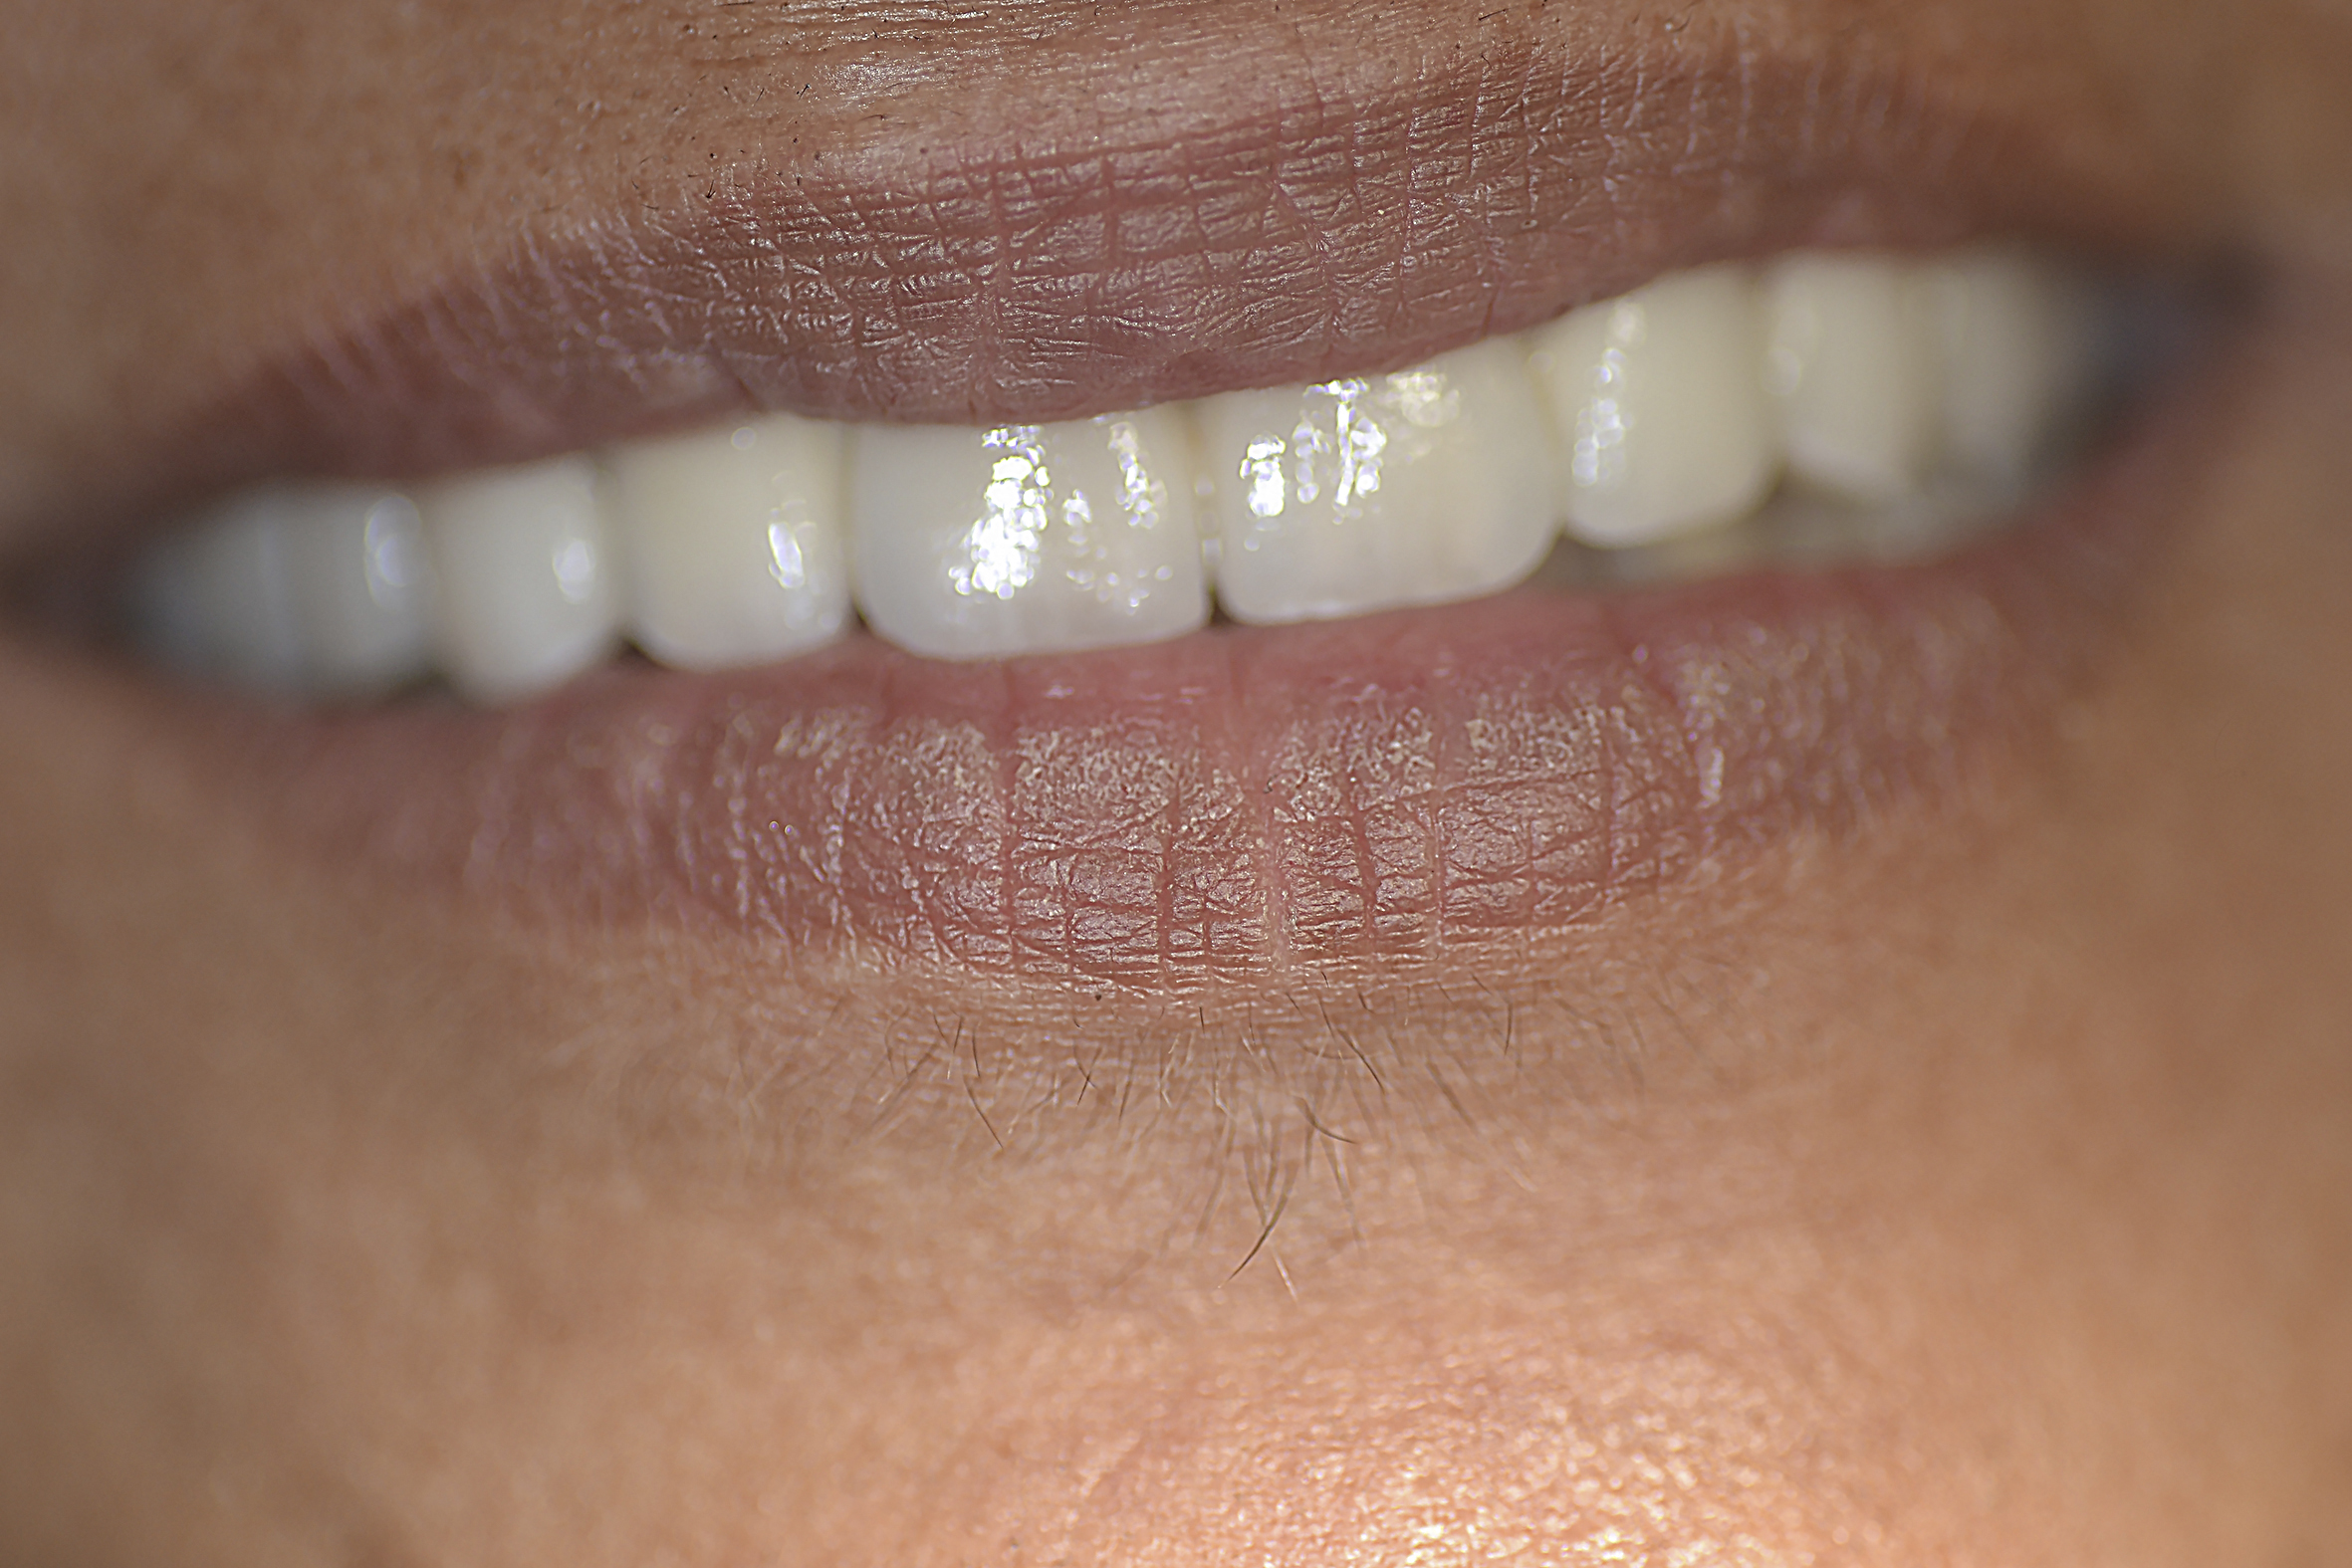

The next stages of prosthetic dental treatments were continued in the regular hospital dental clinic without any relaxants or tranquilizers. However, it is important to note that the patient was regularly using medical canabies. During the try-in of the bridges (Figure 4) the patient was very cooperative and, most significantly, had almost no involuntary movements.

Fig 4. Front view of restoration showing the asymmetric smile line.

Figure 4